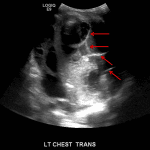

- As the lung fills with fluid, the only remaining air is in the bronchi, which produces air bronchograms – these appear as punctate and linear echogenic foci within the lung (see annotated image #3)